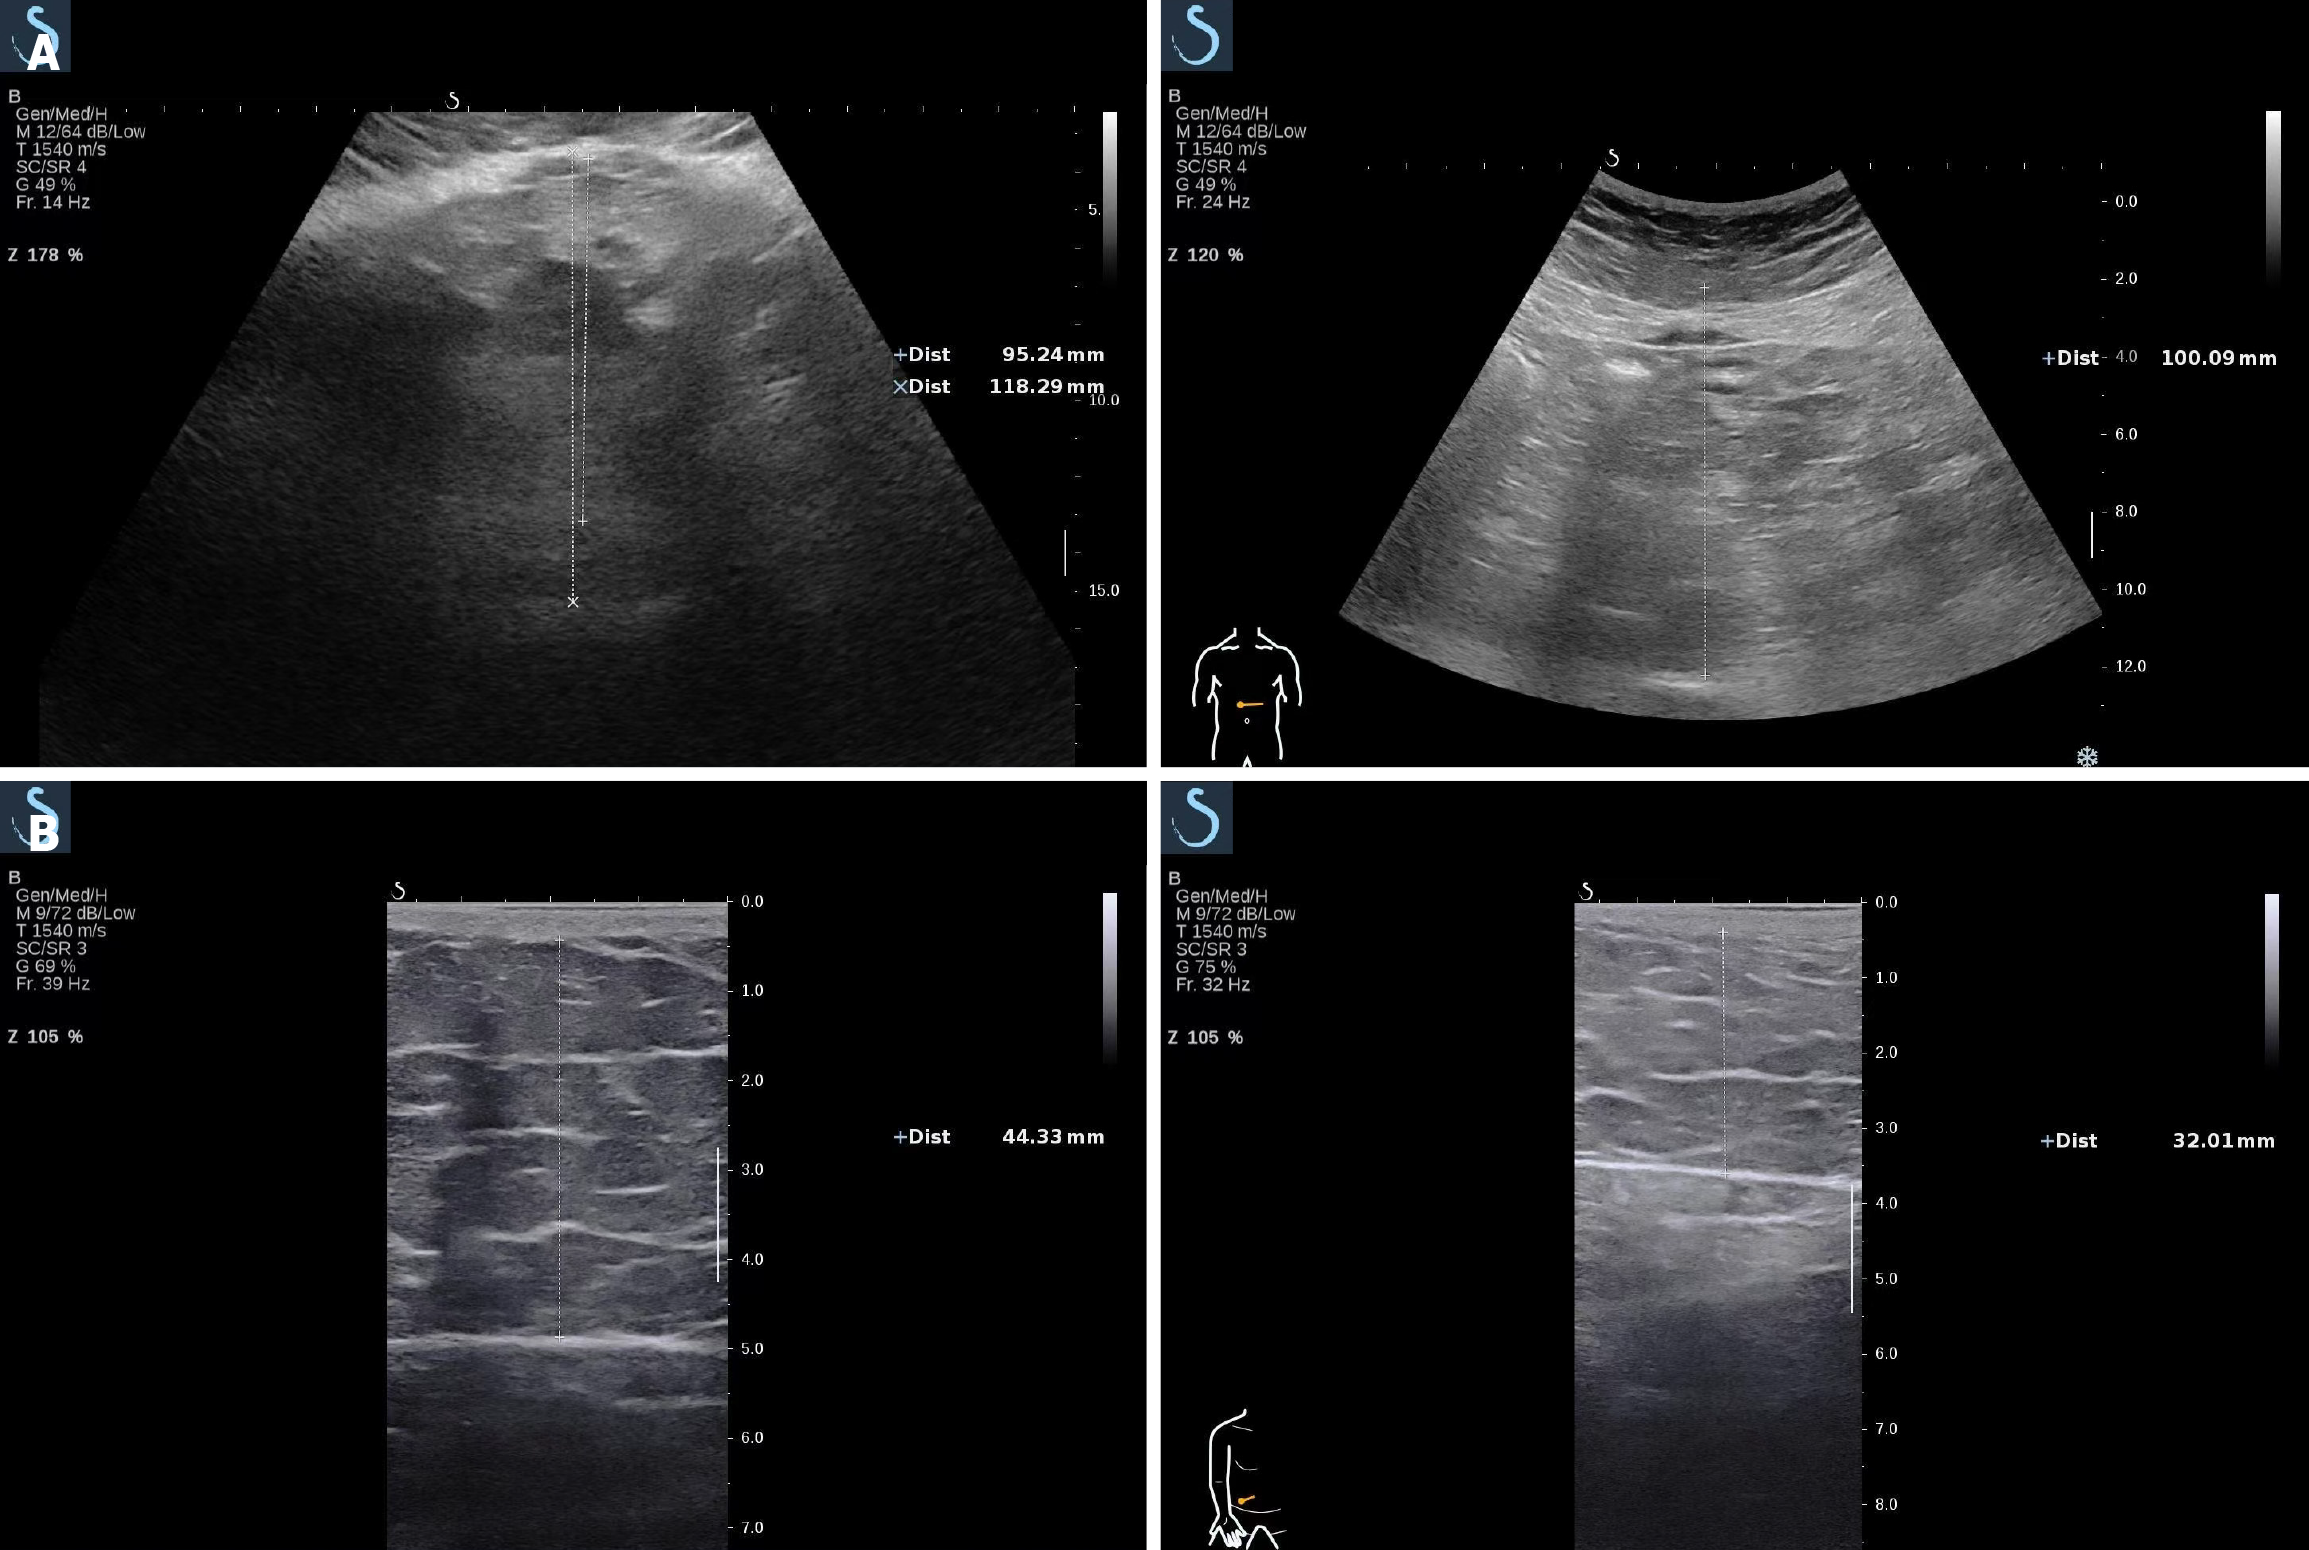

VFT decreased from 118.29 mm to 100.09 mm (Figure 1A), and the right periumbilical SCFT reduced from 44.33 mm to 32.01 mm (Figure 1B). Subjectively, the patient reported increased energy levels, reduced appetite, and significant alleviation of hyperhidrosis and exertional dyspnea.

Figure 1

Figure 1 Ultrasound images. A: Comparative ultrasound images of visceral fat thickness before and after treatment. Ultrasound measurements show a reduction in visceral fat thickness from 118.29 mm pre-treatment (upper image) to 100.09 mm post-treatment (lower image); B: Comparative ultrasound images of right paraumbilical subcutaneous fat thickness before and after treatment. Ultrasound measurements show a reduction in subcutaneous fat thickness from 44.33 mm pre-treatment (upper image) to 32.01 mm post-treatment (lower image).

Ultrasound measurements show a reduction in SCFT from 44.33 mm pre-treatment (upper image) to 32.01 mm post-treatment (lower image).